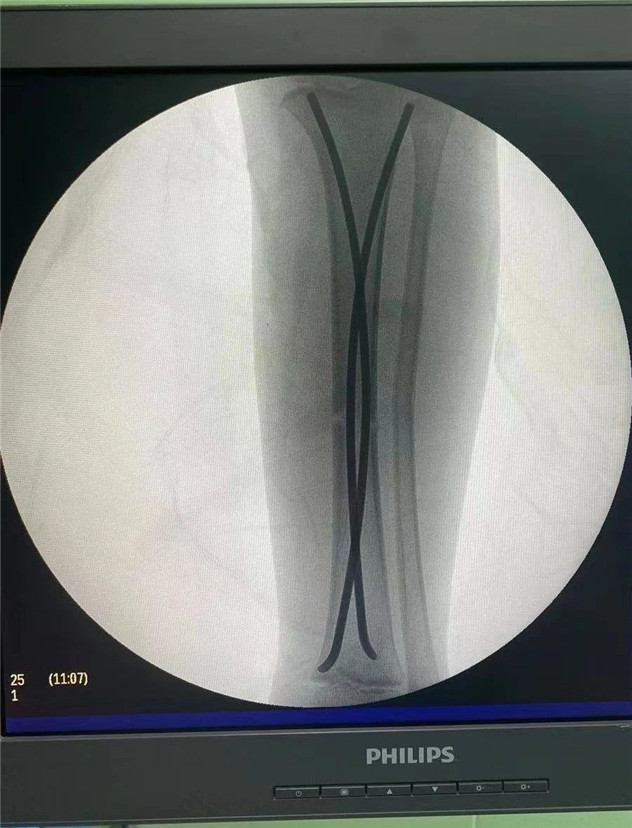

術(shù)中

2020年10月5日,在完成術(shù)前檢查后,睿睿接受了閉合復(fù)位彈性釘內(nèi)固定術(shù),手術(shù)由羅軍主任主刀。術(shù)中只需要兩個(gè)1厘米的小切口,精準(zhǔn)微創(chuàng),僅一個(gè)小時(shí),手術(shù)便圓滿完成。